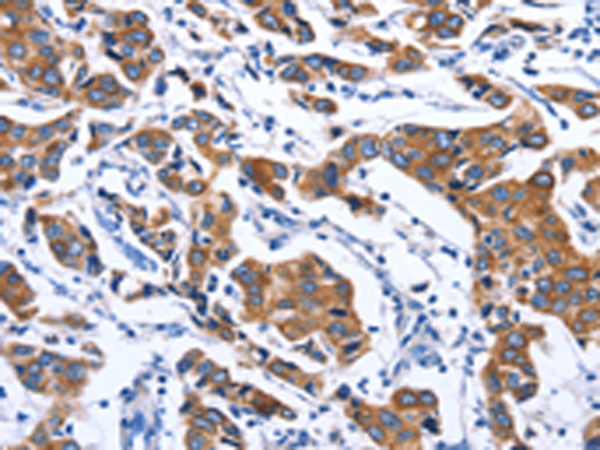

分类: 科研抗体货号: P07452别名: ME; HME; MME; MMP-12应用: WB,IHC反应种属: Human